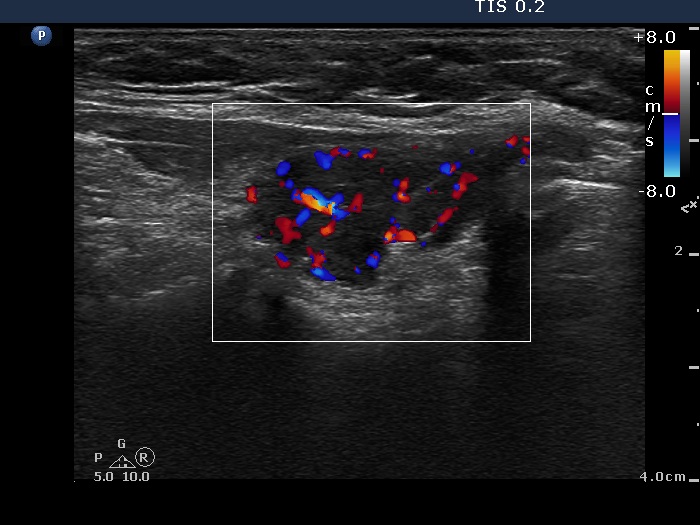

Ultrasonography. Both lobes were composed of a central hypoechogenic part surrounded with an echonormal rim. Although this pattern resembles that of a large hypoechogenic nodule occupying almost the entire lobe, this is one of the characteristic presentations of Hashimoto's thyroiditis. In contrast with a nodule, the borders between the central hypoechogenic area and the surrounding echonormal rim are irregular.